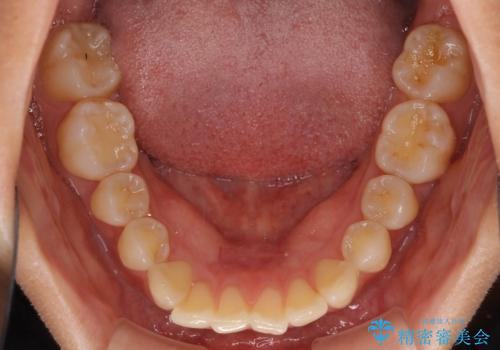

- 前歯の叢生と口元の閉じにくさを気にして来院された患者様です。

奥歯の咬み合わせを見ると、上顎が下顎に対して相対的に前方にありました。

口元の閉じにくさを改善するためには、上顎臼歯を後方に移動させた咬み合わせにする必要があります。

インビザライン単体で改善することも可能ですが、達成する可能性が高くないため、カリエールディスタライザーという補助装置を併用して、より確実性を上げることとしました。

奥歯の咬み合わせを改善しながら、並行してインビザラインで歯列を整えることとしました。

カリエールディスタライザーを併用したことで、確実かつ短期間で治療を終えることができました。